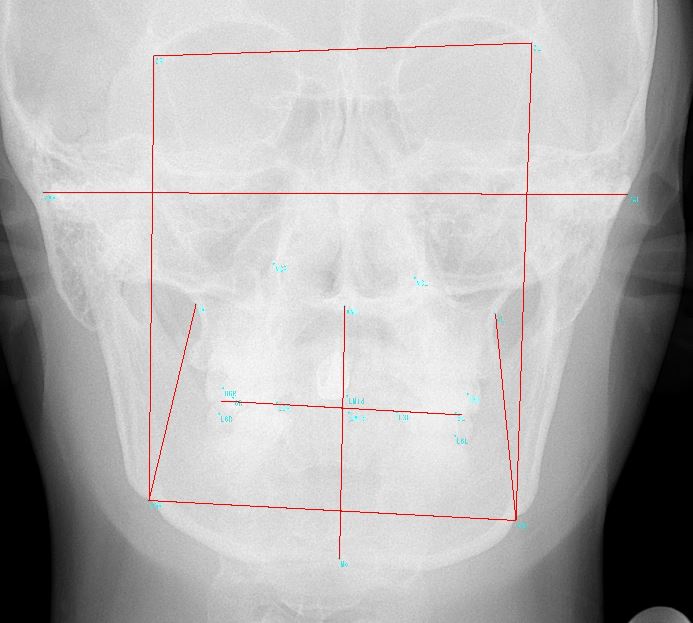

2.レントゲン(パノラマX線写真、側貌セファロ写真、正貌セファロ写真)

👆このセファログラム(頭部X線規格写真)の分析・計測が、矯正歯科の診断では必須であり、重要です!!最近ではCTスキャンを応用する場合もあります。

計測は専門の計測ポイントを利用して、トレースを行い角度や長さを分析します。

計測は専門の計測ポイントを利用して、トレースを行い角度や長さを計測し、分析します。分析方法は色々な方法があり、これは、担当医によって違います(流派のようなものがあります)が、基本的項目は共通しているかと思います。

このレントゲン分析が矯正歯科の診断には必須です。にはこんな感じで行います。